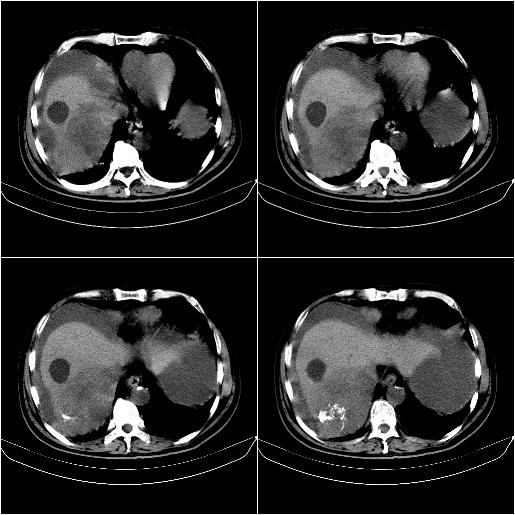

m,67y,肝癌9月,介入术后3月。现腹胀、纳差、腹泻。

门静脉有很大的瘤栓,膈肌及膜膜有转移,不用再做了.

1)肝癌介入治疗术后碘油沉积不良。2)门静脉瘤栓形成,腹膜广泛性转移。3)肝硬化,脾大,腹水。4)慢性胆囊炎。